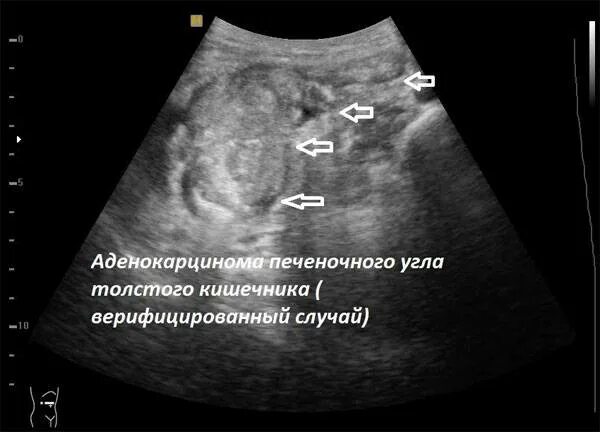

Как выглядит узи живота